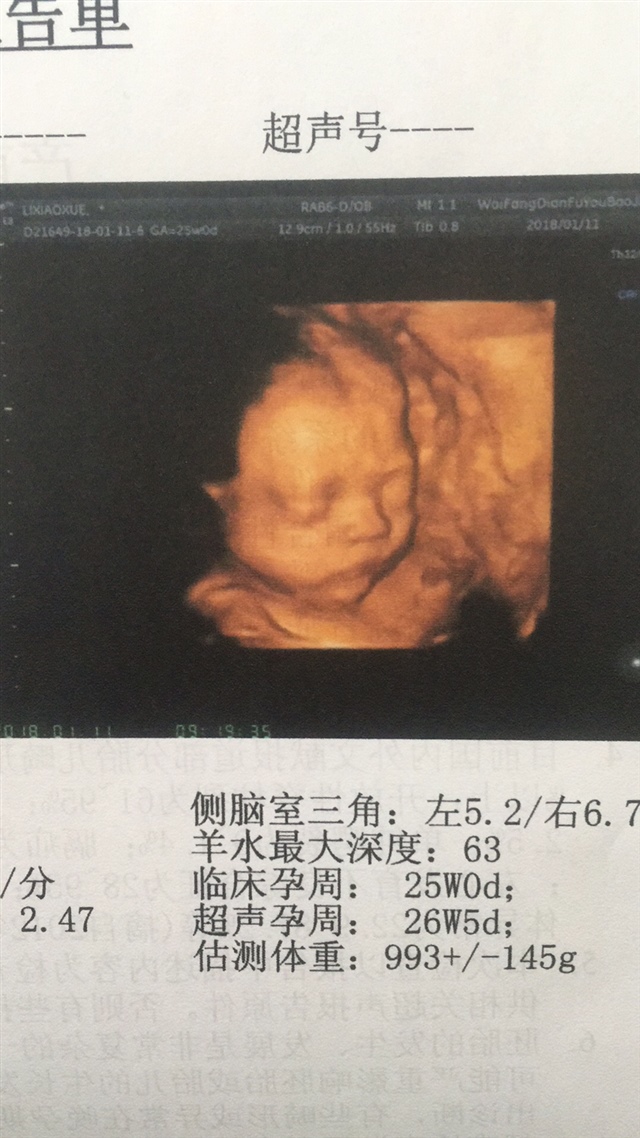

生下来应该更可爱,颜值很高啊